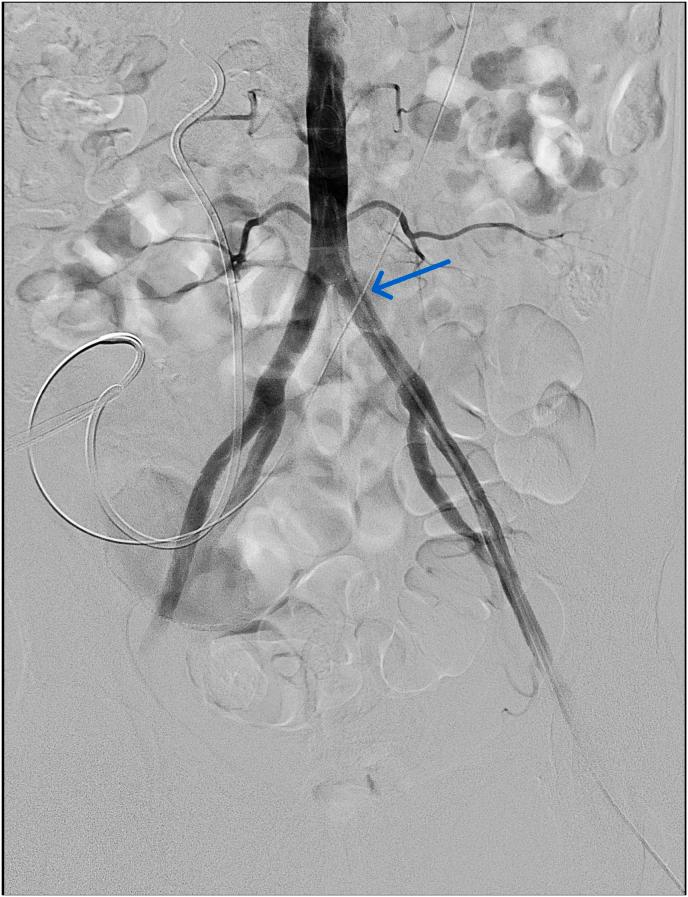

A 56-year-old female experienced massive pulsatile bleeding from the left ureter during routine ureteral stent exchange. She had a history of radical cystectomy and bilateral stent insertion due to uretero-intestinal strictures. Upon stent removal, sudden bleeding through the urostomy led to hypovolemic shock. Urostomy site compression stabilized the patient, and CT revealed suspected ureteroarterial fistula. Angiography confirmed the diagnosis. Covered stent placement in the external iliac artery resolved the condition. No recurrence was observed during a three-year follow-up. Prompt tamponade followed by endovascular intervention can be life-saving in such cases.

一名56岁女性在进行常规输尿管支架置换时,左侧输尿管出现大量搏动性出血。她有根治性膀胱切除术和因输尿管肠道狭窄而双侧置入支架的病史。取出支架后,经造口突然出血导致低血容量性休克。造口部位压迫使患者病情稳定,CT显示疑似输尿管动脉瘘。血管造影确诊了该诊断。在髂外动脉置入覆膜支架解决了该问题。三年随访期间未观察到复发。在这种情况下,迅速压迫止血后进行血管内介入治疗可挽救生命。